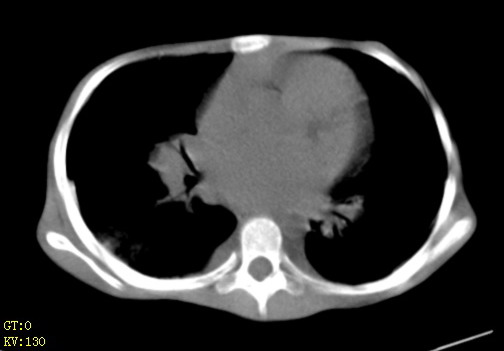

女,12岁,气促、咳嗽2天,3个月前查胸片示:两肺感染,急诊入院查ct,血常规等未检查。

先心(室缺?)、左室大,心功能不全;肺部感染

心衰 肺水肿

1、左心房、左心室增大,考虑左心衰, 2、肺水肿合并感染 3、双侧胸腔积液

双肺中下野不规则片絮状阴影,中外带明显,双侧胸腔少量积液,心影增大,心腔密度减低,隆突下及左侧气管旁见钙化淋巴结影,考虑双肺感染、心衰;建议结合临床除外h1n1并急性心衰,先心不能排除。